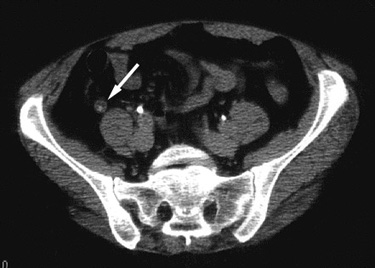

| Perforated appendicitis with generalized

peritonitis and multiple abscesses. 14 year old girl presented with one week history of nausea, vomiting, and fever. A CT scan was performed to evaluate for appendicitis, shown below. |

![]() |

Figure 1. Axial CT image in the upper pelvis shows free intraperitoneal fluid (FF) with enhancement of the peritoneum (black arrows) consistent with peritonitis. A calcified appendicolith (white arrow) is present. |